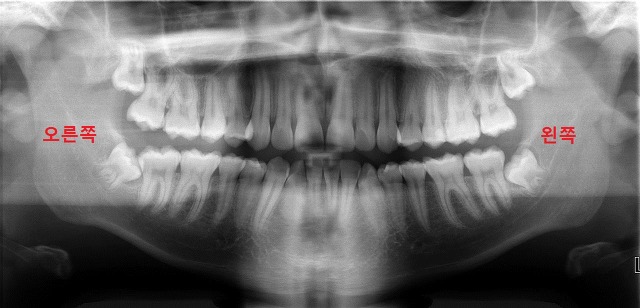

치과에서 나오는 파노라마 사진은 왼쪽과 오른쪽이 반대임. 위에 나오는 사진을 봤을 때

왼쪽=실제 우리 얼굴의 오른쪽

오른쪽=실제 우리 얼굴의 왼쪽

이거임. 그러니까 치과에서 선생님이 자꾸 반대로 말한다고 당황하지 말길